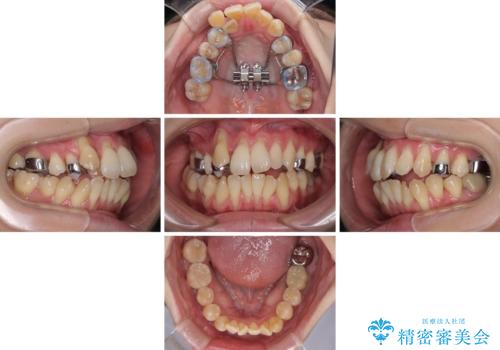

急速拡大装置 狭い骨幅を拡大した上で、顕著なデコボコを改善する抜歯矯正治療

上顎骨よりも下顎骨の幅が広く、更には下顎骨が左側に変位していたため、より良い咬み合わせを達成することを目的として、急速拡大装置を用いて上顎骨を拡大することとしました。

歯根露出が顕著であったため、歯の移動は早く、スムーズに治療を終えられるかと思いましたが、歯槽骨が硬く、治療は長期間に及びました。

過剰に力をかけ続ける事態となり、一部の歯では変色したり、神経が失活したりとトラブルが続きました。

それでも当初とは比べものにならないほど、綺麗な歯列に仕上げることができました。